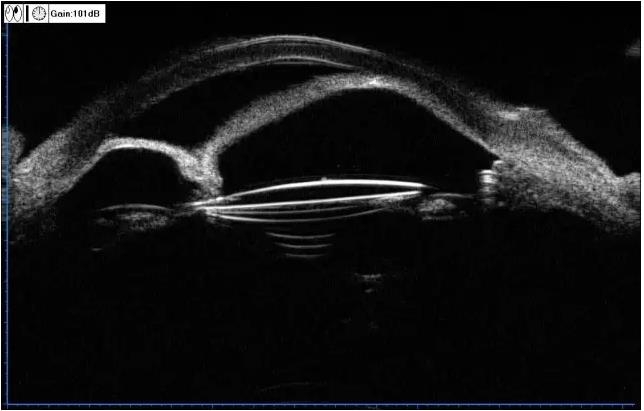

▼两个不同的患者,同样的OCT表现

实用贴:眼科病例高清图片